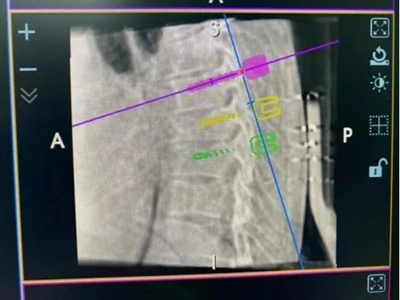

在新技术的配合下,吴宏华完成手术设计,术中采集患者术中3D影像,通过骨科手术机器人拟定椎弓根螺钉打入位置方向后,成功于胸6、7、8椎体置入六枚椎弓根螺钉。术后图像显示,螺钉置入位置与术前规划位置分毫不差,手术微创、精准,圆满成功。

骨科手术机器人完成三维图像信息采集后设计出椎弓根螺钉置入位置及方向